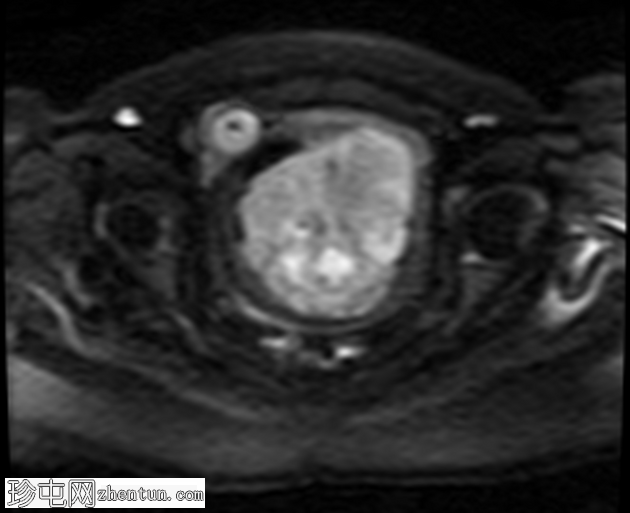

轴位

DWI

病变显示弥散受限区域,DWI信号强度高(等于或高于子宫内膜),实体强化区域ADC映射信号低,测量值小于0.9×10⁻³ mm²/秒(约0.755×10⁻³ mm²/秒)。

影像学特征高度提示平滑肌肉瘤 (LMS),包括中高T2信号强度的实性强化病灶、等于或高于子宫内膜的高DWI信号以及实性强化区域的低ADC值(<0.9 × 10⁻³ mm²/秒)。